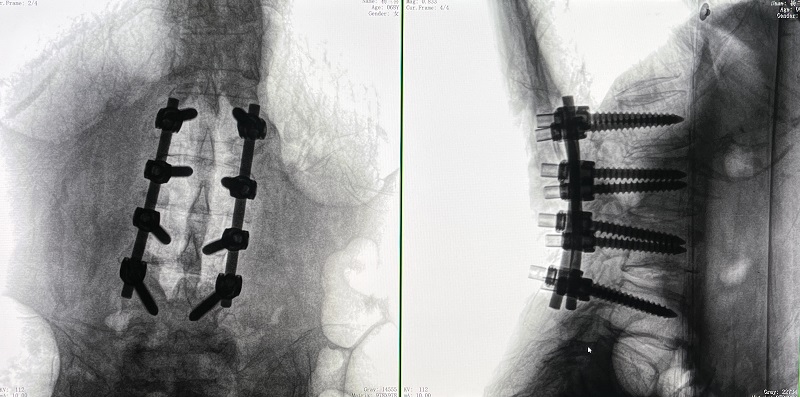

(4)在骨科機器人導航系統輔助下,一次性準確植入8枚椎弓根螺釘。

術后圖像